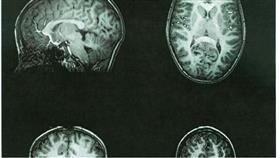

فقد أظهرت دراسة فرنسية أن الدماغ يتأثر بشكل مباشر ويكرس المزيد من الجهد للمؤشرات التي تدل على وجود تهديد.

ولأول مرة توصل الباحثون إلى أن مناطق معينة من الدماغ توجد بها أعصاب مسؤولة عما يسمى الحاسة السادسة تترقب وقوع مكروه وترصده قبل حدوثة بـ 200 جزء من الثانية.

كما لاحظ القائمون على هذه الدراسة بأن الأشخاص شديدي التوتر تختلف لديهم مناطق رصد المخاطر عن نظرائهم ذوي الأعصاب الهادئة ويتجاوبون معها بطريقة مختلفة ومناطق أخرى في الدماغ عن طريق تحديد ماهية الخطر بعكس الفئة الأخرى التي تحدده عن طريق تعابير الوجه.